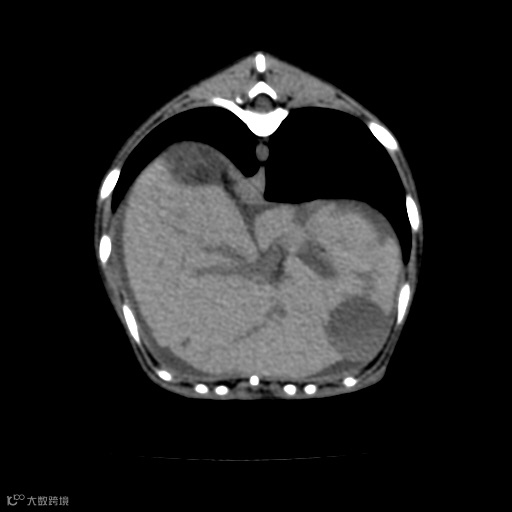

图像中不同组织和结构之间的灰度差异。观察图像中相邻组织的灰度差异,并确保没有过度和欠度对比的情况。良好的对比度能够清晰地显示不同组织的边界和细节。

肝实质/肝内血管清晰